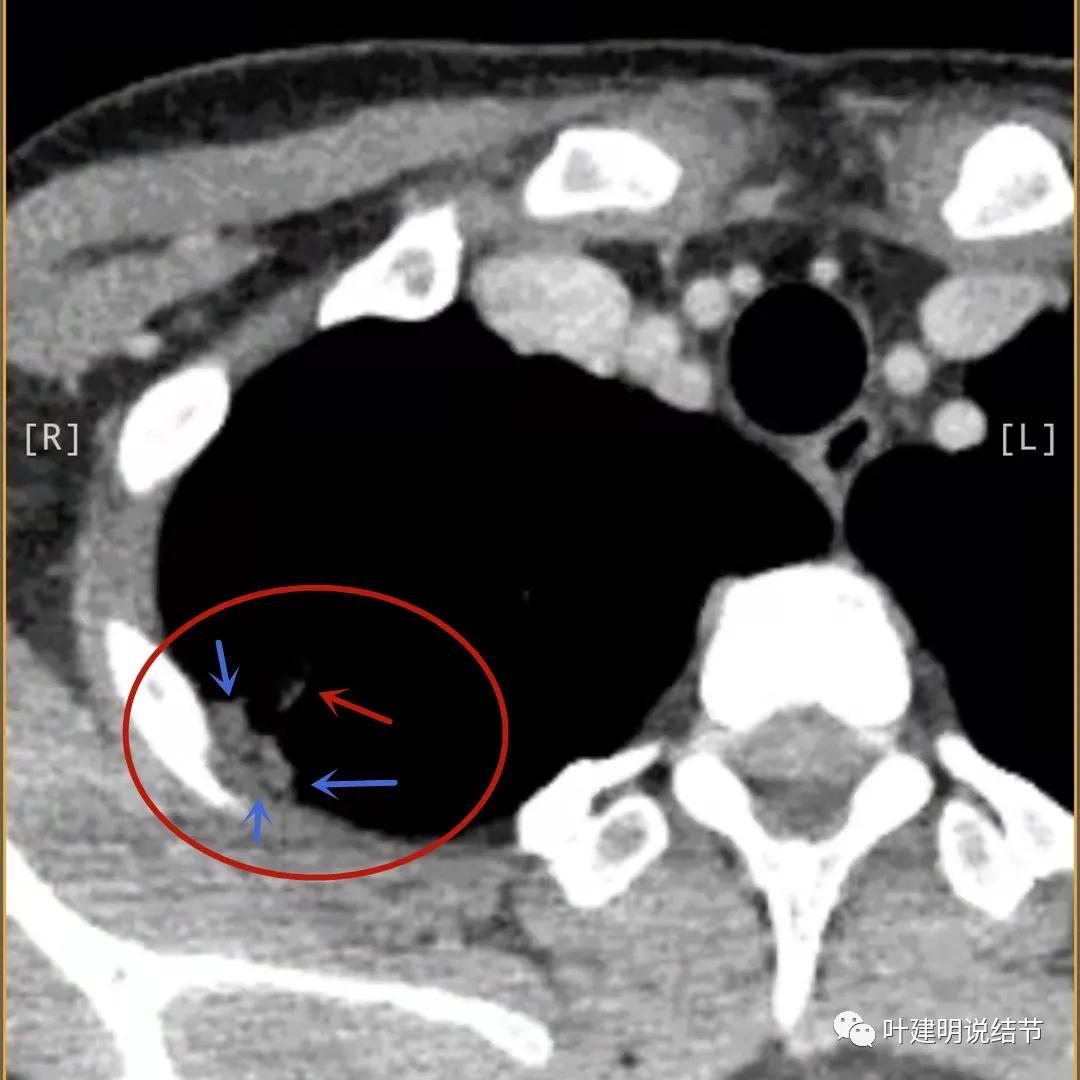

蓝色箭头所指处居然有低密度影,难道是坏死?因为比肌肉密度低,也无强化,况且主病灶的中间也有个低密度的小点状

病灶有明显强化(说明炎性可能性大,如果恶性这样强化,血供丰富,应该倍增速度更快。蓝色箭头示胸膜处低于软组织密度的区域;桔色箭头示病灶边缘平直缺乏膨胀性;黄色箭头示中间的空腔

邻近胸膜处的增厚密度低于肌肉组织,病灶强化明显且均匀

上图示空洞偏心,而且红色箭头所指处与空腔似乎是整合,而非囊壁生长增厚。天蓝色箭头示近胸膜处的低密度区域,考虑坏死成分,囊壁的邻近部分也是极低密度区域,也可能是干酪样坏死区

贴胸膜侧也是有强化的,这里可不是结节主病灶所在